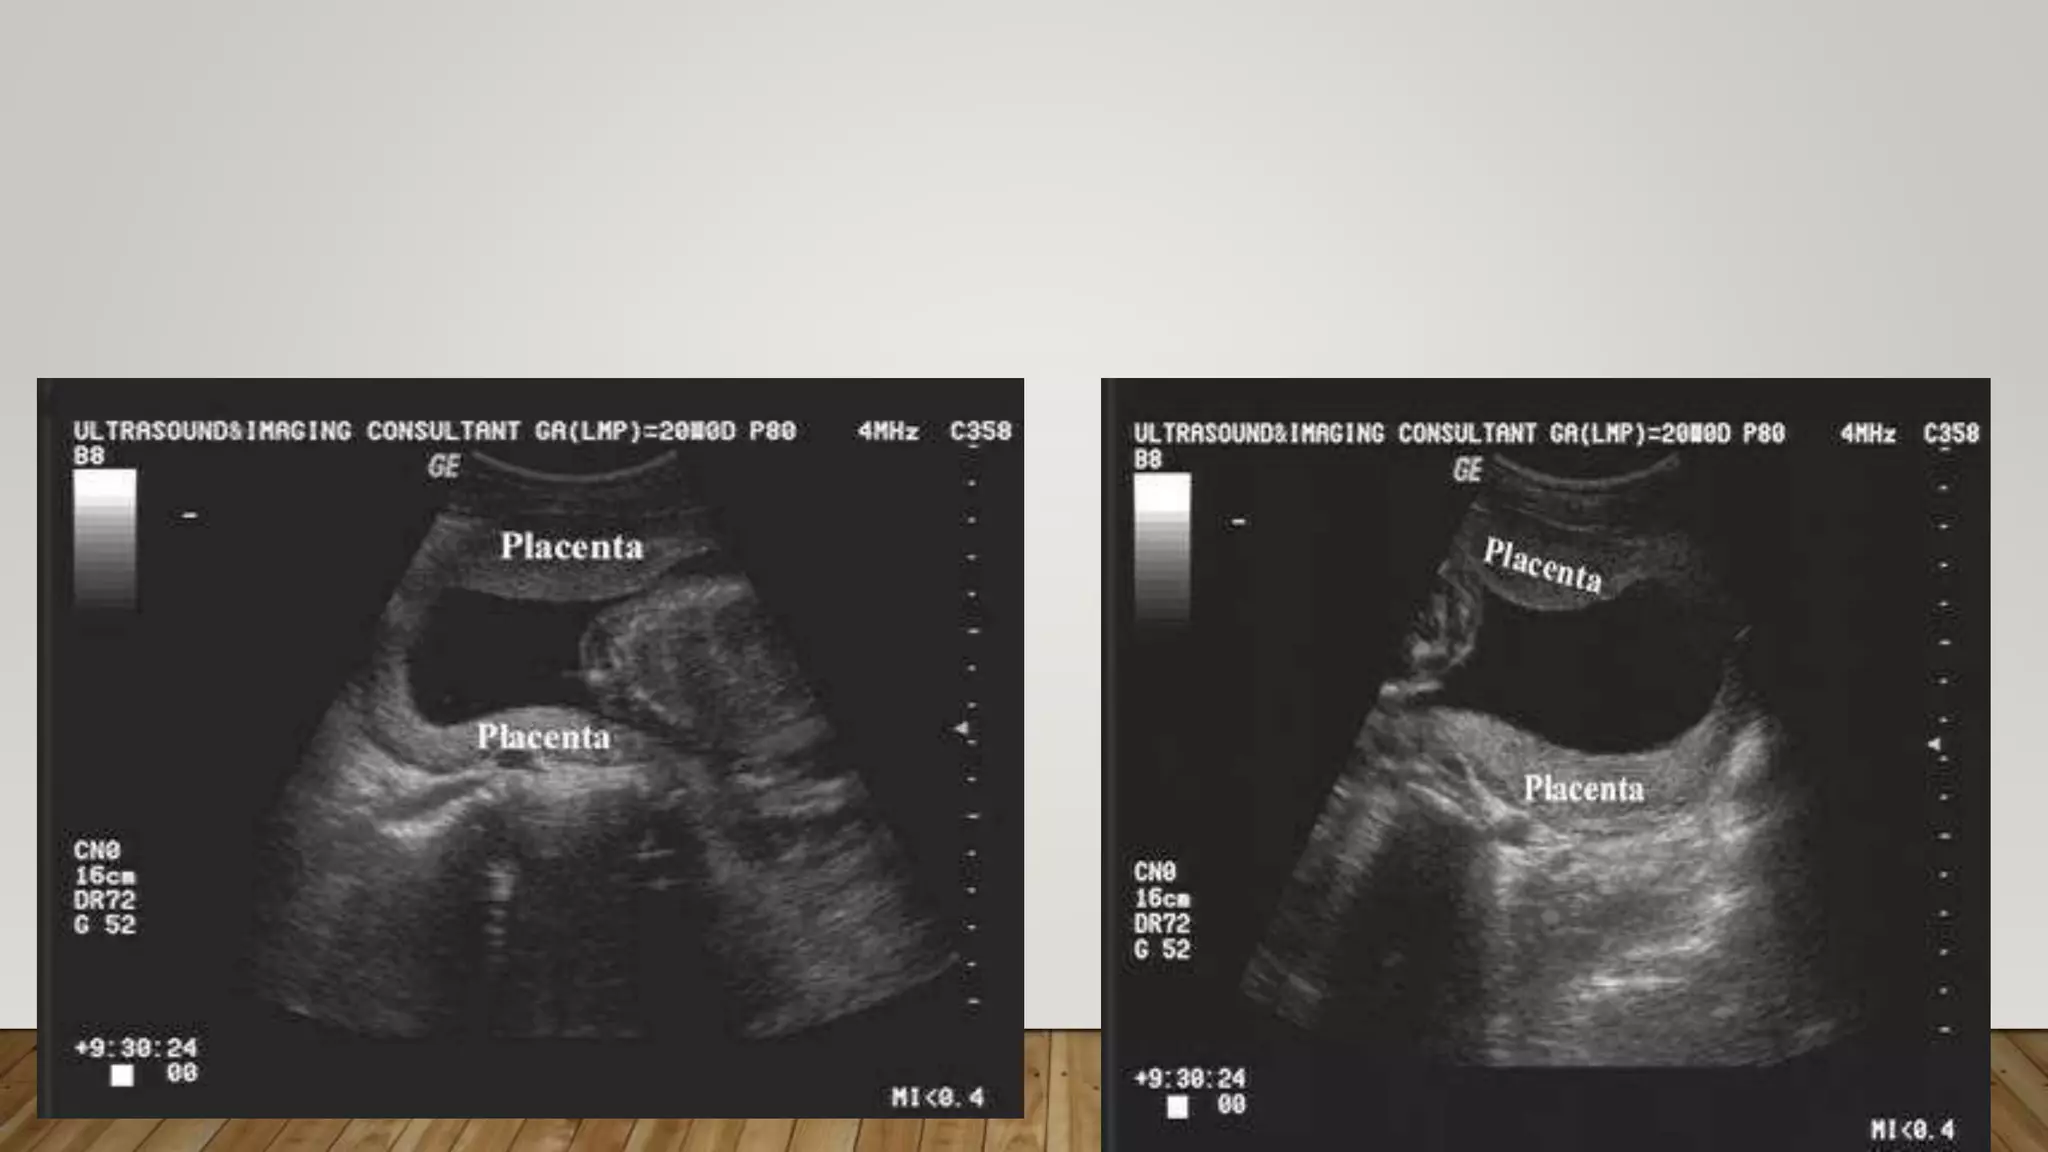

These are two views of a bilobate placenta, where each of the lobes (one on the anterior and one on

the posterior aspects of the uterine cavity) are marked with an *